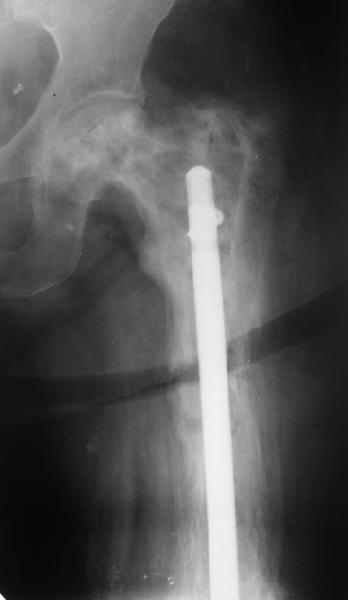

Еще один пример. Пациентка с юга России, прислала рентгенограммы через год. На сегодня прошло 2 г. 8 мес. после операции. Несмотря на не очень убедительный процесс сращения, пациентка ходит. Учитывая остеопороз при Педжете, решили, что динамизировать вообще не нужно.

При переломах на фоне болезни Педжета металлоконструкция часто служит эндопротезом, несущим нагрузку. Динамизация индивидуальна,- по рентген-динамике. Основной упор- на медикаментозную терапию- см. канд. дисс. Колондаева А.Ф.

Стержень можно было бы поставить подлиннее.